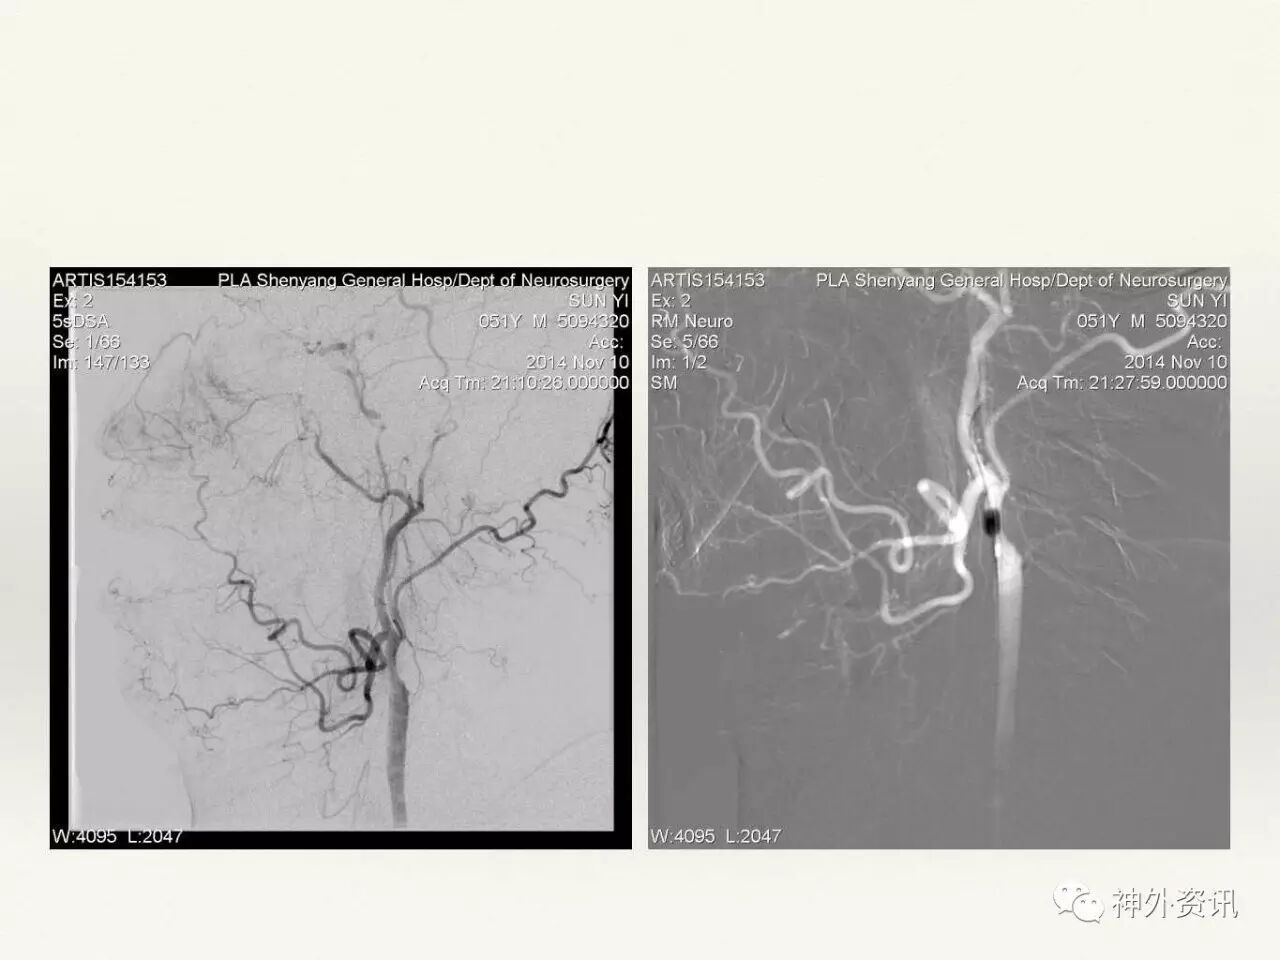

在东北地区率先开展了颈内动脉、大脑中动脉及基底动脉闭塞血管内再通、颅内动脉栓塞急性期取栓、血流导向装置治疗大型宽颈动脉瘤等,对颅内动脉瘤、动静脉畸形、颈动脉及颅内动脉狭窄、颈内动脉海绵窦瘘、硬脑膜动静脉瘘等外科治疗具有较深的造诣。完成脑血管造影8600余例,各类脑血管病介入手术共4500余例,动脉瘤、动静脉畸形、脑肿瘤、脑出血及脑外伤等外科手术1500余例。